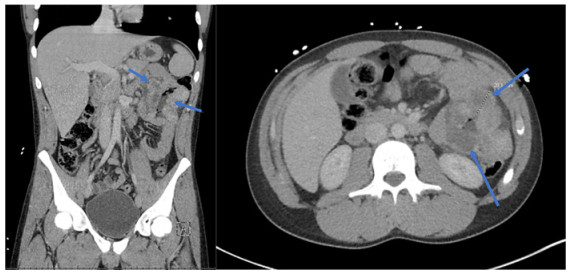

Jejunal Leiomyosarcoma in a Young Adult: Distinguishing from Gastrointestinal Stromal Tumor through Radiographic, Histologic, and Epidemiologic Analysis – A Case Report